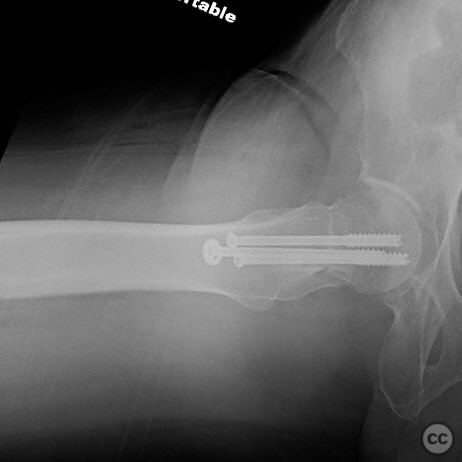

Clinical and radiological findings:  A 62-year-old male presented following a fall from standing height, resulting in a displaced subcapital femoral neck fracture. The patient has a complex medical history including substance abuse (methamphetamine and cocaine), cirrhosis, diabetes, and open draining foot wounds. Radiographs confirmed a displaced femoral neck fracture, classified as AO/OTA 31-B2.

The surgeon emphasized the importance of achieving an anatomical reduction and avoiding varus malalignment during fixation. The decision to pursue percutaneous fixation was influenced by the patient's high risk for complications with arthroplasty due to his comorbidities and lifestyle factors. The potential for conversion to hemiarthroplasty was considered if fixation failed.

Orthopaedic implants used:   Cannulated screws